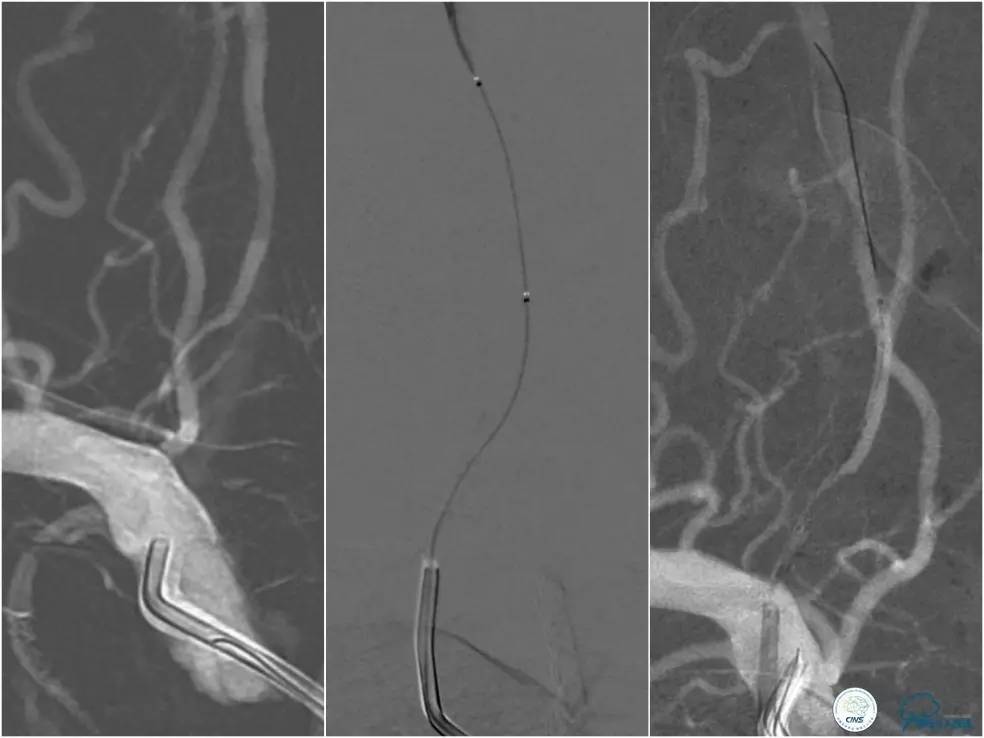

全麻下右侧股动脉穿刺置入8F动脉鞘,6F导引导管到位,送入Traxcess(0.014″200cm)微导丝+Echelon-10微导管小心通过右侧椎动脉V1段狭窄处至V2段远端,交换撤出Traxcess微导丝,送入Transend(0.014″300cm)微导丝至V2段远端(图10)。

图10

Ultra-Soft球囊(3.0mm×20mm)于狭窄处预扩张后置入EXCEL支架(4.0 mm× 24mm),球扩后造影见支架贴壁良好,远端血管显影好,前向血流TICI3级。6F导引导管沿微导丝通过右椎动脉V1段支架至V2段(图11)。

图11

此时多体外投照显示右椎V4-基底动脉极重度狭窄,几近闭塞(图12)。

图12